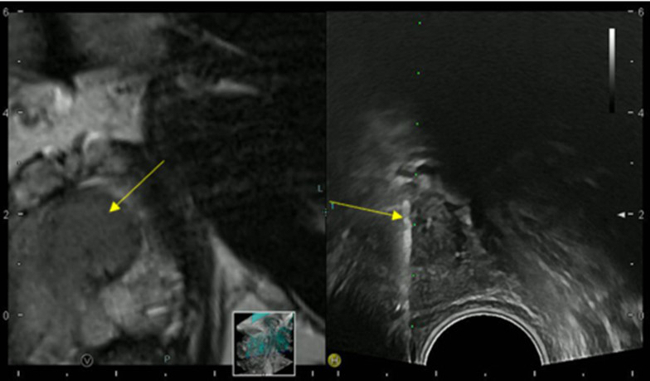

Imaging and Targeted Biopsy of the Genitourinary (GU) Tract

Friedrich Aigner

- Fusion imaging of the GU-tract

- Fusion targeted biopsy of the prostate

The use of fusion imaging in uroradiology improves ultrasound lesion-detection rates, shows more reliable size controls at different time points, is an alternative to in-bore biopsies (Fig. 11) and can be used for focal therapy.